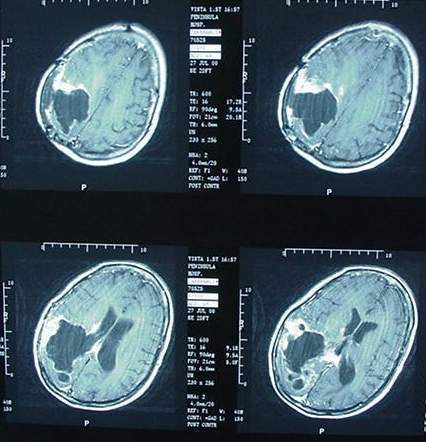

Cette nouvelle étude parue le 24 décembre dans le Journal of Neuroly and Neurophysioly projette que d'ici 15 ans, selon l'hypothèse basse d'une réduction de la faculté de l'ADN à se réparer ou au contraire selon l'hypothèse haute d'une mutation de l'ADN, l'augmentation des cancers du cerveau est susceptible d'augmenter d'un facteur 2 (100% d'augmentation) à 25 (2400% d'augmentation).

Figure 3. Taux de tumeurs cérébrales en Norvège ajustés selon l'âge par 100.000 personne-ans par année civile avec 3 hypothèses au sujet du téléphone portable 1) Dommages accrus de l'ADN (rouge) 2) pas de réparation de l'ADN (magenta) et 3) n'a aucun effet (vert).